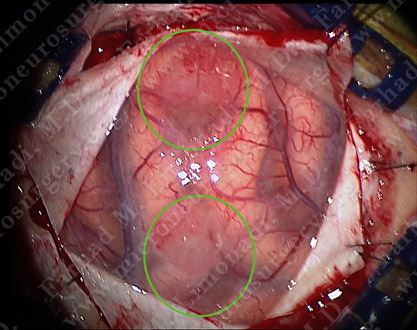

He underwent surgical resection of both of these nodular enhancing tumors utilizing brain mapping, cortical stimulation, stereotactic and computer navigation, and intraoperative neurophysiological monitoring.

View through the surgical microscope shows two nodular tumors (outlined by green circles).